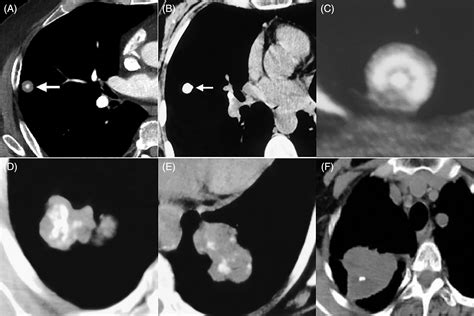

• Chest X-ray: A chest X-ray can reveal the presence of calcium deposits in the lungs.

• CT Scan: A computed tomography (CT) scan provides detailed images of the lungs and can help identify the location and extent of the calcification.